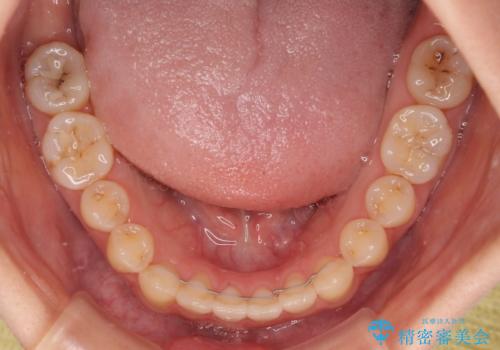

オープンバイトは舌の突出癖により誘発され、治療後も突出癖が残っている容易に後戻りしてしまいます。

治療期間を短縮するためにも、舌突出癖の改善が極めて重要となります。

特にインビザラインではIPRという歯と歯の間を削る処置を多用するため、後戻りによりスペースが生じやすくなるため、治療初期段階での舌のトレーニングが必須となります。